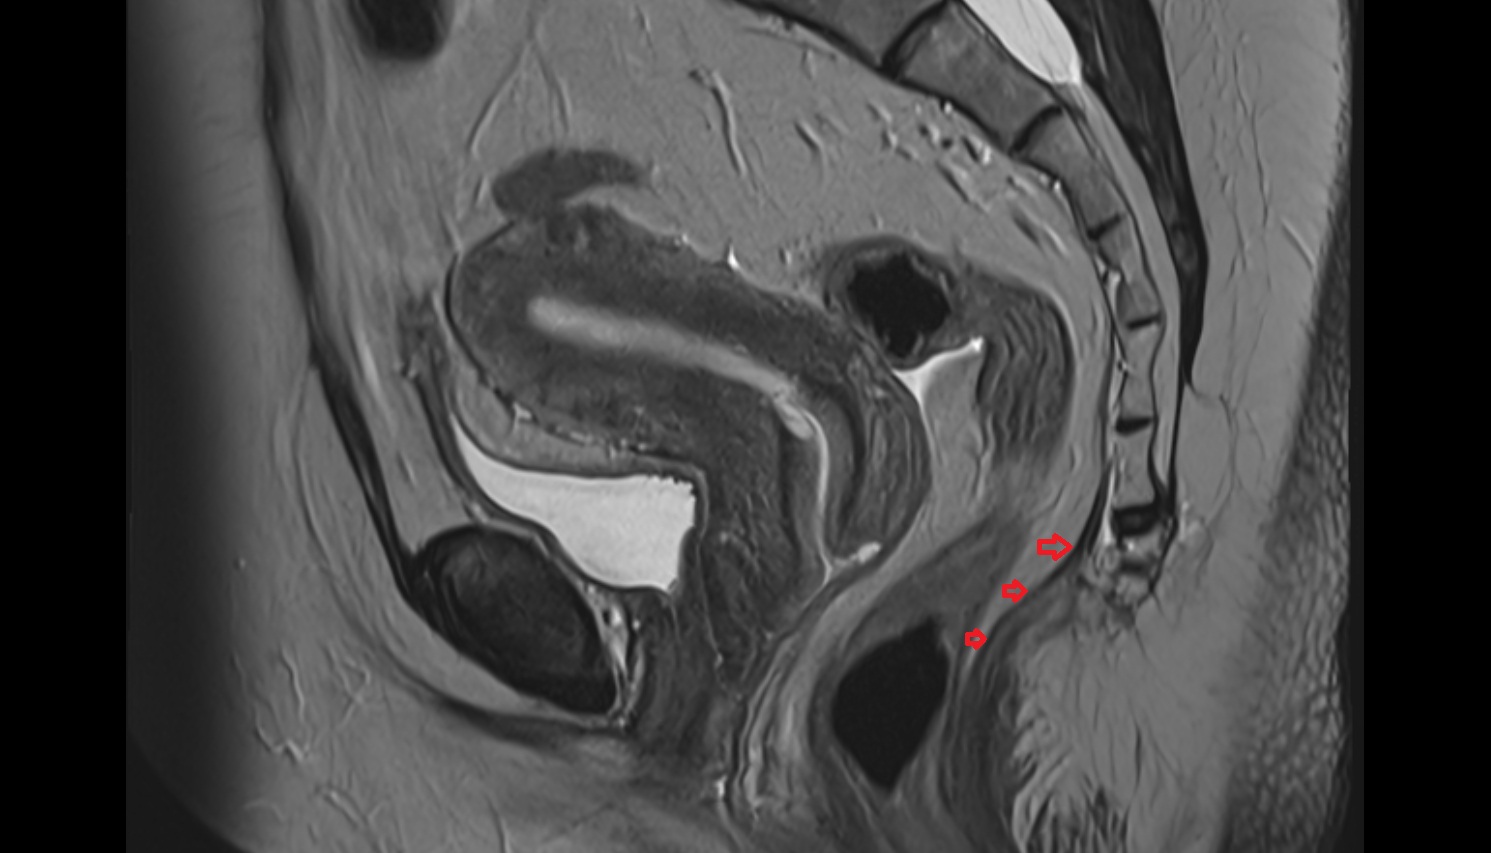

- Uterus

- Body of uterus

- Fundus of uterus

- Cervix of uterus

- Isthmus of uterus

- Vagina

- Fornix of the vagina

- Endometrium of uterus

- Myometrium of uterus

- Perimetrium of uterus

- Junctional zone of uterus

- Rectum

- Urinary bladder

- Vesicouterine pouch

- Rectouterine pouch (pouch of Douglas)